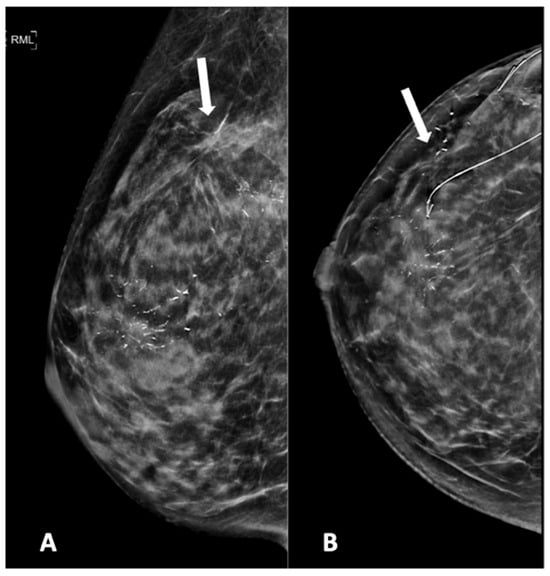

Figure 2, Figure 3, Figure 4, Figure 5 and Figure 6 show examples of the different microcalcification morphologies and distributions, while Figure 6 shows an example of a mammographic mass and an image of a complementary ultrasound assessment of the mass.

Figure 5.

Mammogram study of a right breast in (A) MLO view and (B) CC view, showing branching pleomorphic calcifications in a segmental distribution in the upper outer-to-mid quadrant, reported as a BI-RADS 4C lesion. A stereotactic-guided hook-wire insertion was performed (hook-wire in CC view), and an HPE of the wide local excision showed invasive carcinoma. We noted an architectural distortion in the upper outer quadrant (arrow) from a previous surgery.